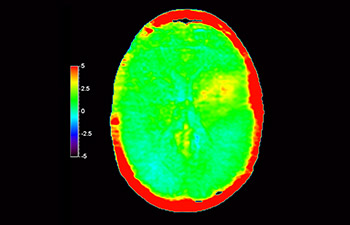

Astrocytoma

Brain astrocytoma, post-radiotherapy

with 3D APT

3D APT (Amide Proton Transfer) is a unique, contrast-free, brain MR imaging method addressing the need for more confident diagnosis in neuro oncology. 3D APT uses the presence of endogenous cellular proteins, to produce an MR signal that directly correlates with cell proliferation, a marker of tumoral activity. 3D APT can support trained medical professionals in differentiating low grade from high grade gliomas and, in differentiating tumor progression from treatment effect1.